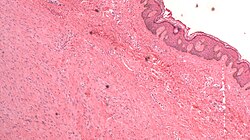

Lipoid proteinosis

A. Inner labial biopsy shows subepithelial hyalinized pink/red material, about blood vessels and in general. B. The particularly glassy appearance of the material in areas is evident at high power.